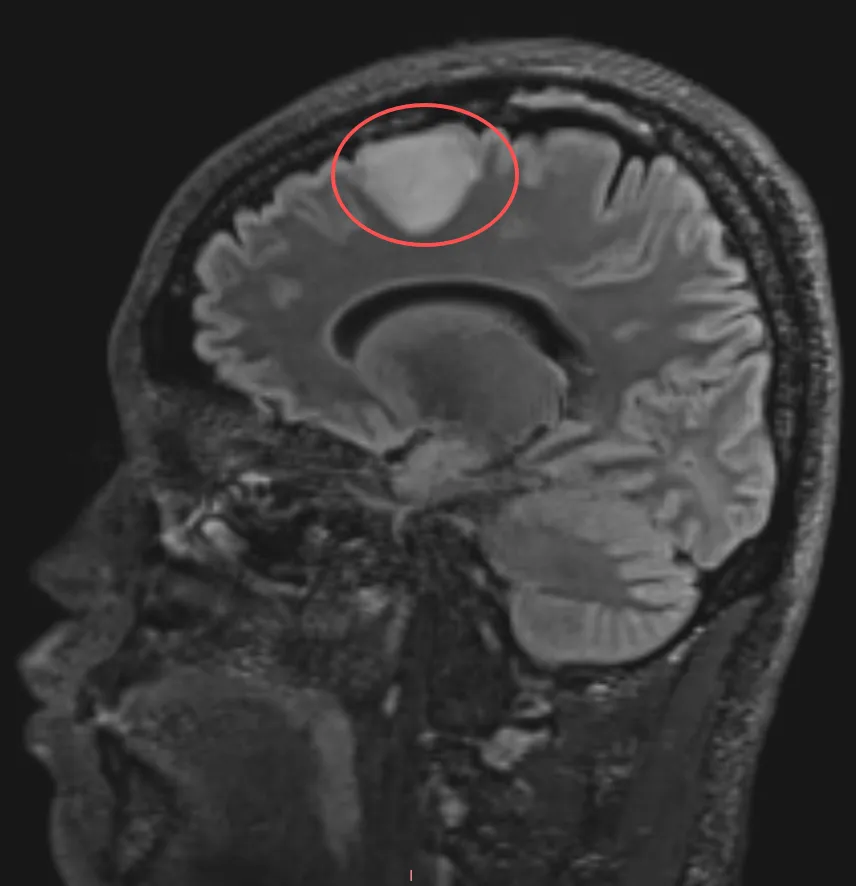

刚过而立之年的郑先生从未想过体检查出一个脑瘤,27×23mm的病灶位于额上回区域,紧邻中线。这里存在一个“辅助运动区”(SMA),比如你想要去拿起咖啡杯时,在动手之前,辅助运动区会发出指令:“把手移到这里。”如果受损,患者可能就会想要移动却无法完成动作。

我们知道脑胶质瘤是中枢神经系统常见的肿瘤。手术切除是延缓肿瘤复发、延长患者生存时间的重要治疗手段,经典的神经外科教材均提到对于胶质瘤手术,必须尽可能实现肿瘤全切除。然而,胶质瘤手术一直以来面临的难点是:如何既切除了肿瘤,又保护大脑功能?开颅手术没有容错,尤其是第一次手术做的好与不好直接影响预后。于郑先生而言,这台手术他要为自己争取万无一失的把握,人生只有一次,他不希望一丝一毫的偏差影响到以后的生活质量。